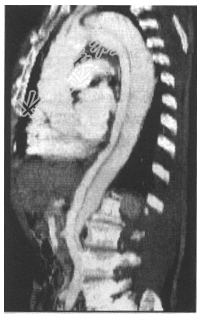

- 简答题2、该患者CT增强扫描如下图所示,请问影像诊断是什么?

- 简答题3、请对该病的影像学表现进行叙述。